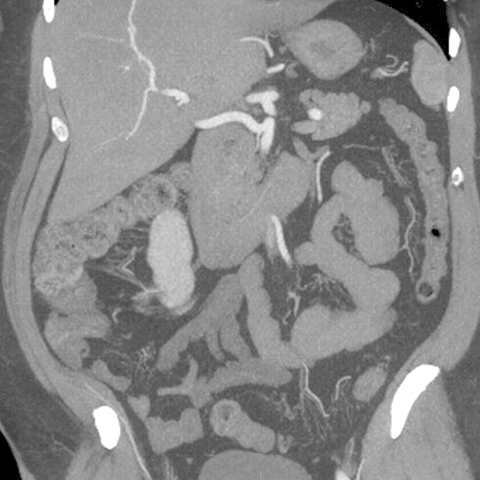

Normal Appendix, CT (coronal) [3 of 6]